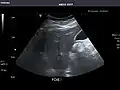

Right kidney -

Kidneys: Right and left kidneys measure 11.5 cm and 12 cm in length respectively. No hydronephrosis. Small left lower pole kidney cyst.